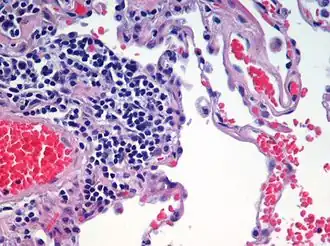

Microanatomy

The lungs are part of the lower respiratory tract, and accommodate the bronchial airways when they branch from the trachea. The bronchial airways terminate in alveoli which make up the functional tissue (parenchyma) of the lung, and veins, arteries, nerves, and lymphatic vessels.[3][15] The trachea and bronchi have plexuses of lymph capillaries in their mucosa and submucosa. The smaller bronchi have a single layer of lymph capillaries, and they are absent in the alveoli.[16] The lungs are supplied with the largest lymphatic drainage system of any other organ in the body.[17] Each lung is surrounded by a serous membrane of visceral pleura, which has an underlying layer of loose connective tissue attached to the substance of the lung.[18]

Alveoli

Alveoli consist of two types of alveolar cell and an alveolar macrophage. The two types of cell are known as type I and type II cells[32] (also known as pneumocytes).[3] Types I and II make up the walls and alveolar septa. Type I cells provide 95% of the surface area of each alveoli and are flat ("squamous"), and Type II cells generally cluster in the corners of the alveoli and have a cuboidal shape.[33] Despite this, cells occur in a roughly equal ratio of 1:1 or 6:4.[32][33]

Type I are squamous epithelial cells that make up the alveolar wall structure. They have extremely thin walls that enable an easy gas exchange.[32] These type I cells also make up the alveolar septa which separate each alveolus. The septa consist of an epithelial lining and associated basement membranes.[33] Type I cells are not able to divide, and consequently rely on differentiation from Type II cells.[33]

Type II are larger and they line the alveoli and produce and secrete epithelial lining fluid, and lung surfactant.[34][32] Type II cells are able to divide and differentiate to Type I cells.[33]

The alveolar macrophages have an important role in the immune system. They remove substances which deposit in the alveoli including loose red blood cells that have been forced out from blood vessels.[33]